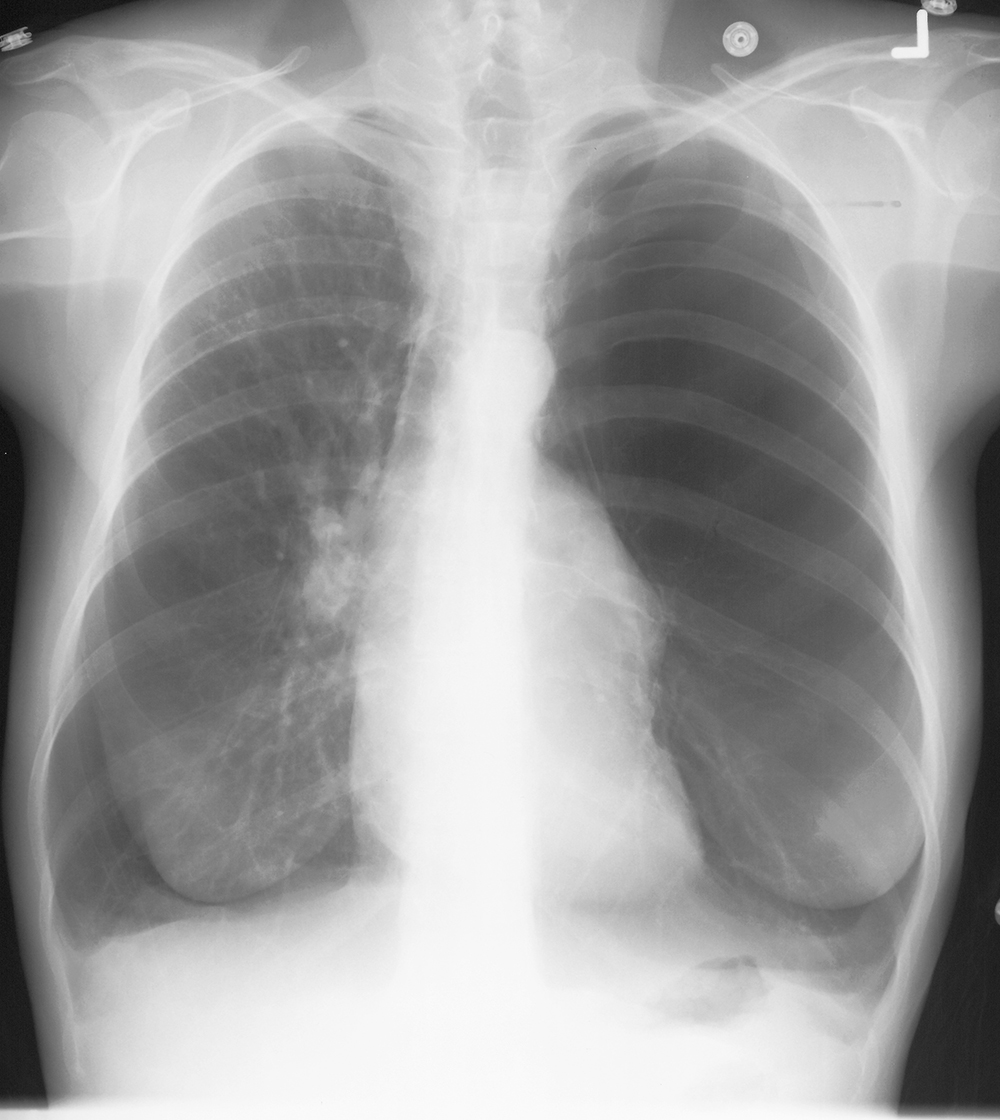

intermediate case for PTX